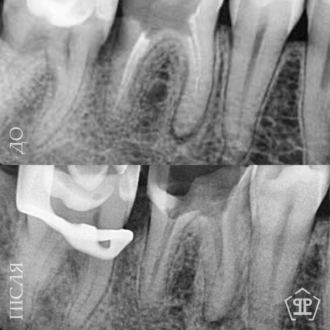

Роботи лікаря Все работы ⋅⋅⋅